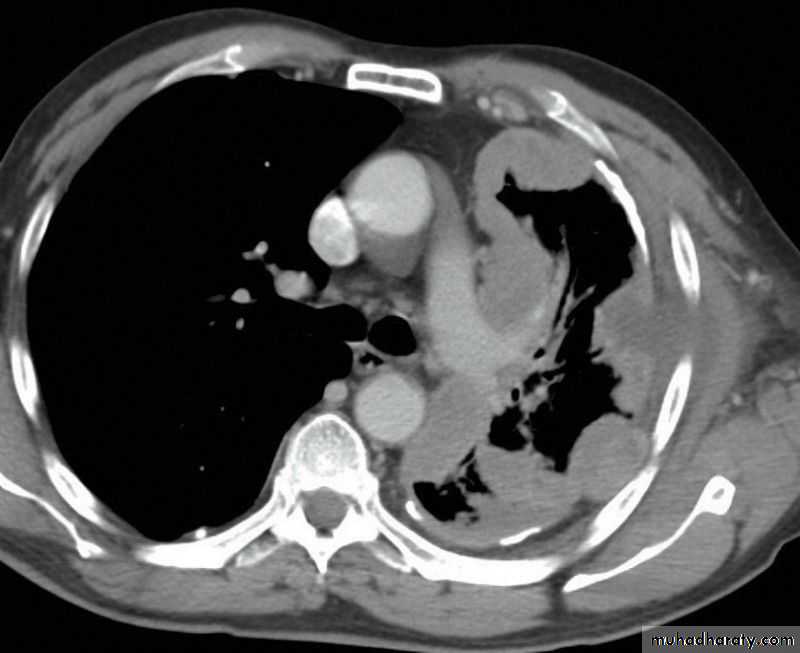

(Collapse) (Massive plural effusion)

Secondary metastasis